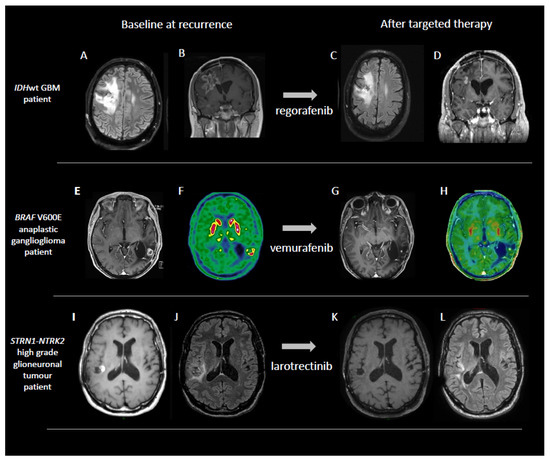

- Berzero, G.; Bellu, L.; Baldini, C.; Ducray, F.; Guyon, D.; Eoli, M.; Silvani, A.; Dehais, C.; Idbaih, A.; Younan, N.; et al. Sustained Tumor Control with MAPK Inhibition in BRAF V600-Mutant Adult Glial and Glioneuronal Tumors. Neurology 2021, 97, e673–e683. [Google Scholar] [CrossRef]

- Boyer, J.; Birzu, C.; Bielle, F.; Goulas, C.; Savatovsky, J.; Karachi, C.; Idbaih, A. Dramatic Response of STRN-NTRK-Fused Malignant Glioneuronal Tumor to Larotrectinib in Adult. Neuro-Oncology 2021, 23, 1200–1202. [Google Scholar] [CrossRef] [PubMed]

- Kaley, T.; Touat, M.; Subbiah, V.; Hollebecque, A.; Rodon, J.; Lockhart, A.C.; Keedy, V.; Bielle, F.; Hofheinz, R.D.; Joly, F.; et al. BRAF Inhibition in BRAFV600-Mutant Gliomas: Results From the VE-BASKET Study. J. Clin. Oncol. 2018, 36, 3477–3484. [Google Scholar] [CrossRef] [PubMed]